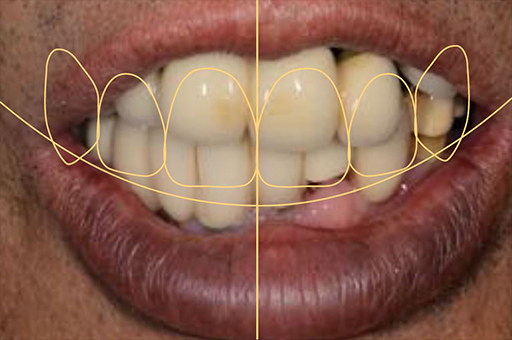

治療前01

治療前02

治療前03